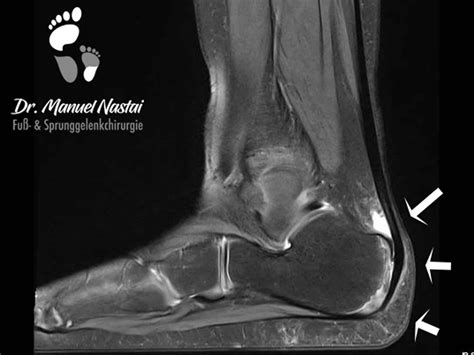

Right Ankle after Surgery Haglund Deformity Mri Stock Photo - Image of ...